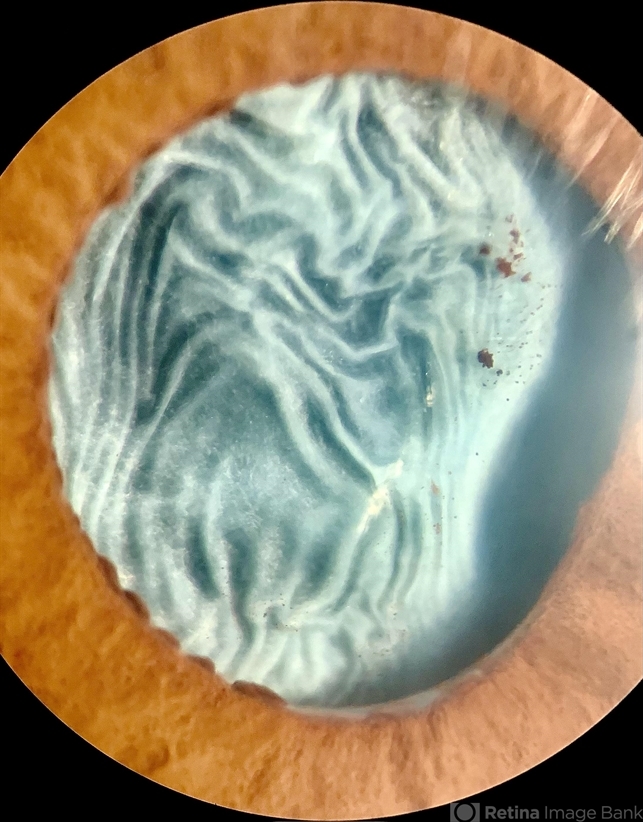

- lens opacity

- Photo slit lamp biomicroscope

- Imprint of Iris Pigmentation on Anterior Lens Surface with wrinkled anterior capsule